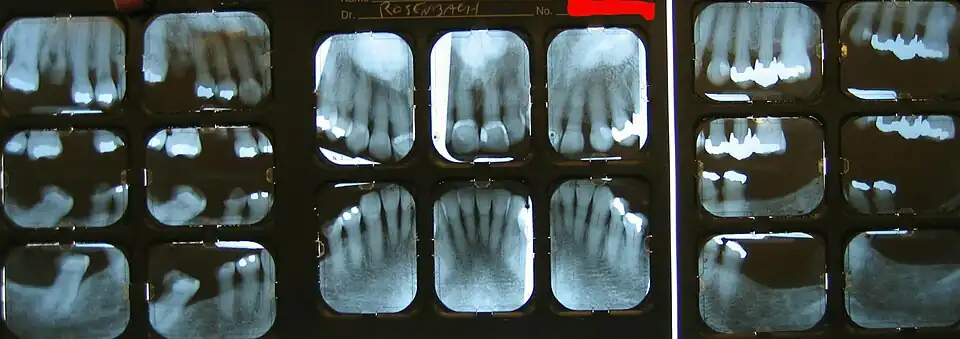

Unter einem Röntgenstatus versteht man in der Zahnmedizin die Anfertigung von Einzelröntgenaufnahmen des Gesamtgebisses.

Die Darstellung aller zahntragenden Abschnitte des Ober- und Unterkiefers erfolgt durch eine Serie intraoraler Zahnaufnahmen. Die Aufnahmen können sowohl in analoger als auch in digitaler Form erfolgen. Die Vorteile gegenüber einem Orthopantomogramm (OPG) liegen in der hohen Detailerkennbarkeit der Einzelaufnahmen gegenüber dem OPG, der Vermeidung von Überprojektionen im Frontzahnbereich, von Verzerrungen und einer Vergrößerung der Abbildung.[1]

Der Röntgenstatus besteht aus 6 bis 14 Aufnahmen. Im Milchzahngebiss genügen sechs Aufnahmen, im Wechselgebiss zehn Aufnahmen. Im bleibenden Gebiss zehn bis vierzehn Aufnahmen, einschließlich sogenannter Flügelbissaufnahmen (engl.: Bite wing) zur Kariesdiagnostik.